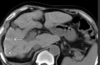

Perda do sinal do fígado em paciente com hemocromatose primária acentuada.

Na TC o achado de aumento da atenuação é inespecífico, encontrado também em diversas outras doenças (uso de amiodarona, sais de ouro, doença Wilson)

• Confirmação diagnóstica;

• Quantificação da sobrecarga férrica;

• Determinar severidade;

• Monitorar terapia;

• Diferenciar hemocromatose primária e secundária.

Graduação da sobrecarga férrica na RM.